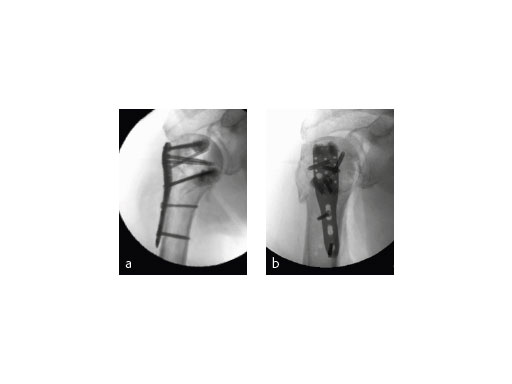

The patient was placed in supine position, having the shoulder on two shoulder supports. After closed reduction of the shoulder, ORIF was performed via an anterior deltopectoral approach using the PHILOS. Four screws were augmented with Traumacem V+ under fluoroscopic control. Initially the treated shoulder was immobilized in a sling for 2 days followed by a pain-adapted functional treatment (Fig 6).

The X-ray review at 3 months after surgery showed an anatomic reduction of the fracture, nicely formatted augmentation, no secondary loss of reduction, and range of motion of the arm reaching the horizontal plane (Fig 7).